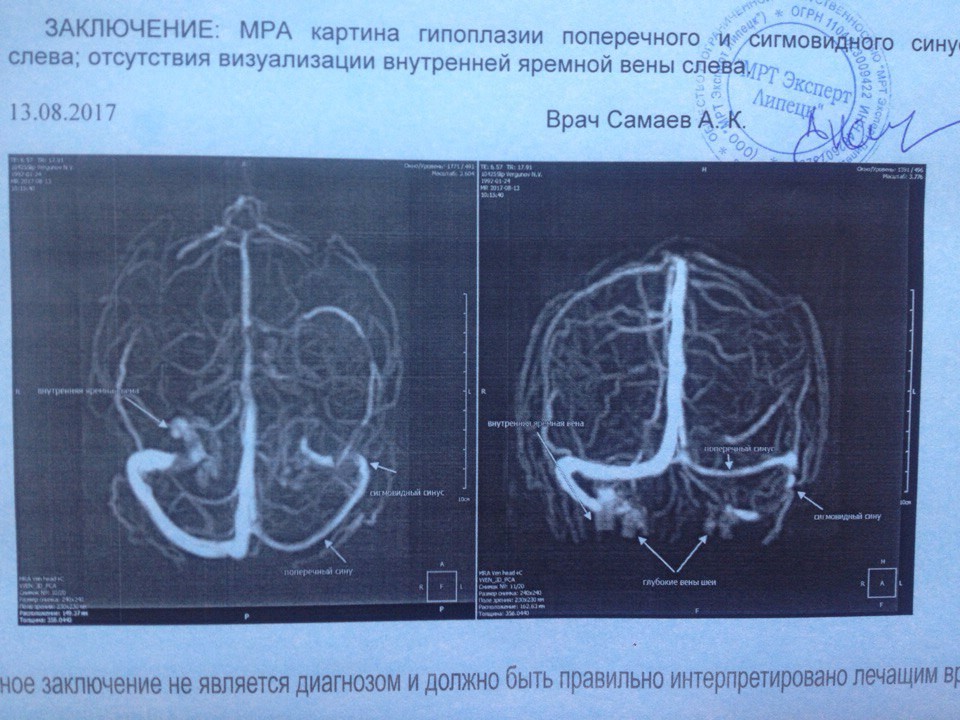

Анатомия внутренней яремной вены: КТ изображения